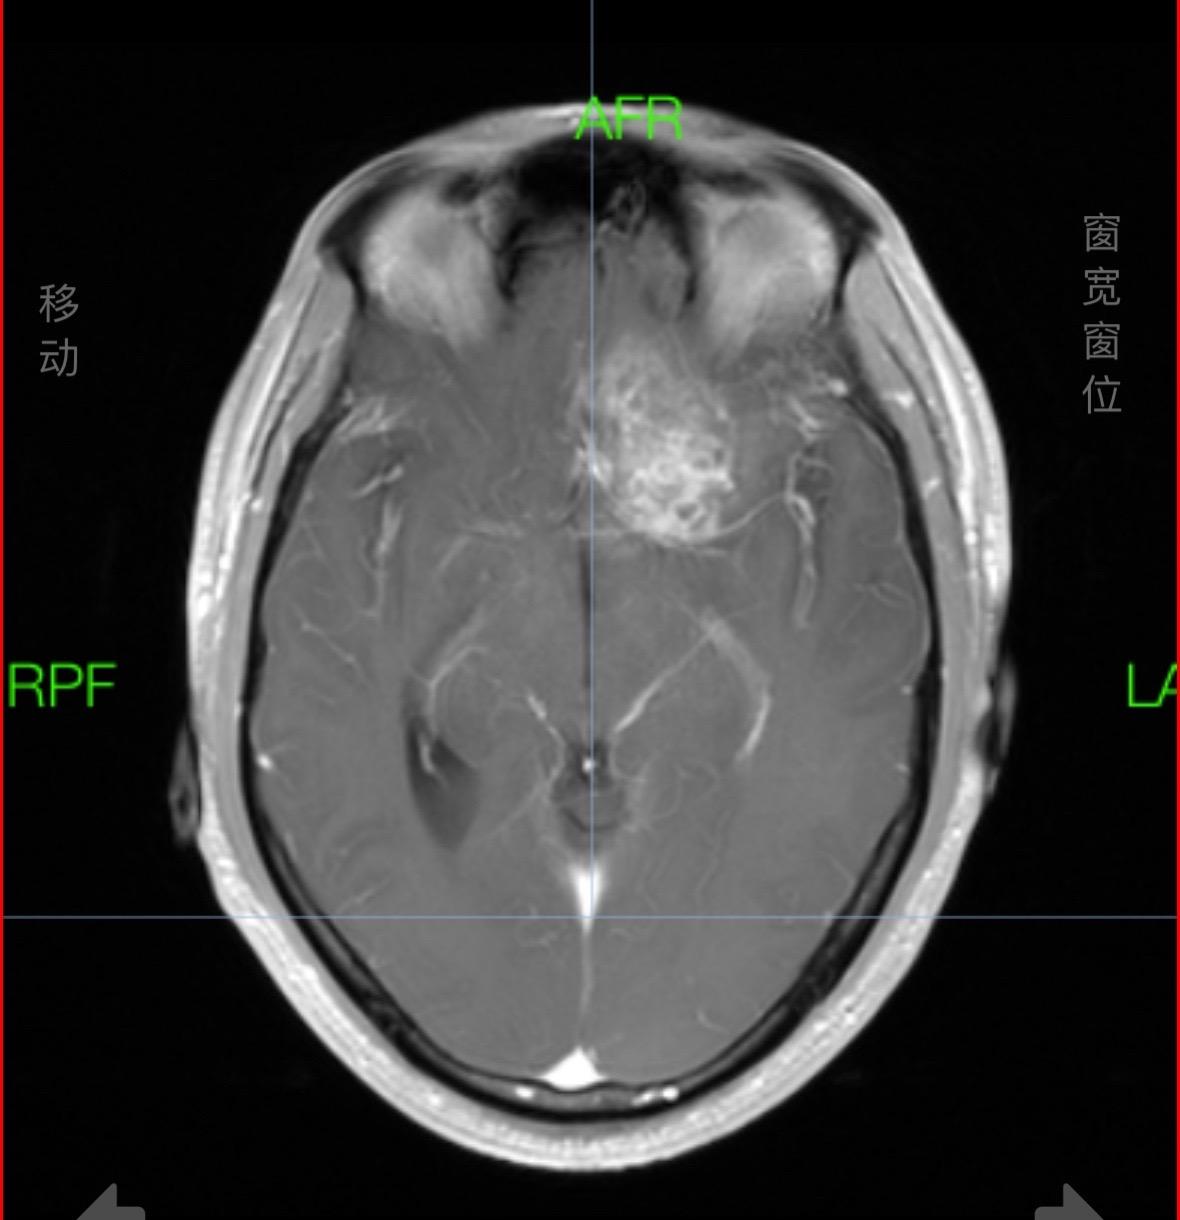

堪比科幻大片---侵袭性垂体瘤。采用显微镜与神经内镜相结合处理垂体瘤...